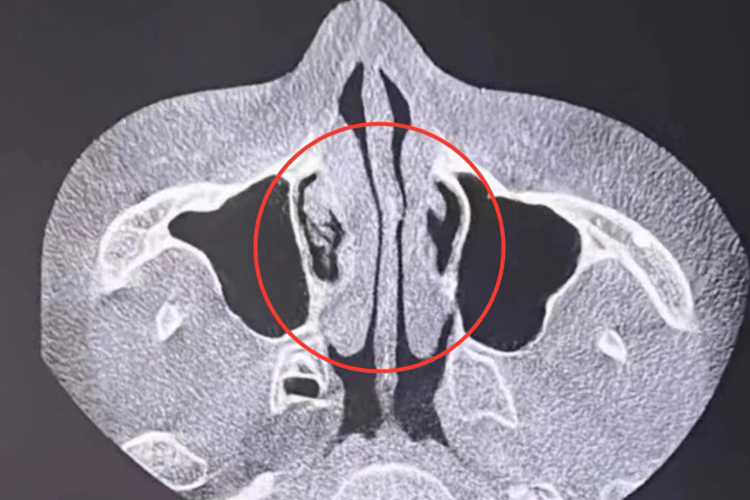

慢性肥厚性鼻炎:慢性肥厚性鼻炎患者发病时,CT检查可见鼻腔黏膜增生、肥厚,下鼻甲肿大,骨质增生,鼻腔狭窄,部分患者可伴有鼻腔结构异常。

变应性鼻炎:变应性鼻炎患者发病时,CT检查可见鼻甲肥大,窦腔黏膜肥厚,鼻腔通气截面积缩小,鼻腔鼻窦可有少量积液。